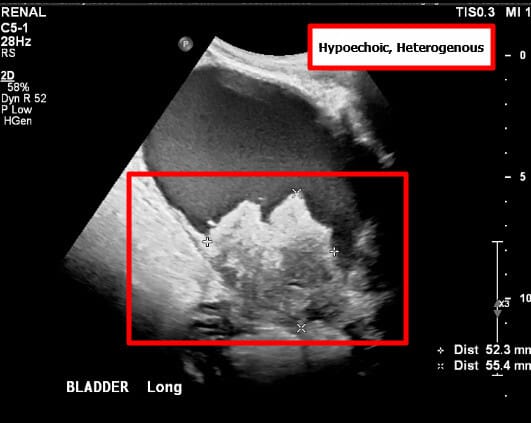

고환암 영상 소견

– 신체검사: 단단한 고환 종괴 촉지.

– 종양표지자: hCG 상승 가능, 그러나 AFP는 정상

– 영상검사: 고환 초음파에서 저에코성 종괴 확인.

– CT/MRI: 병기 설정 및 전이 평가.

– 확진: 고환 절제술(근치적 고환 절제술, radical orchiectomy)을 통한 조직학적 확인.